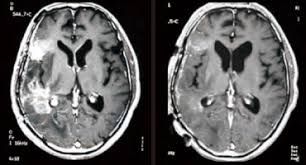

재발성 뇌종양, 특히 교모세포종은 치료가 매우 까다로운 암입니다.

특히 교모세포종과 같은

난치성 뇌종양은 수술·방사선·항암치료 후에도 재발률이 매우 높습니다.